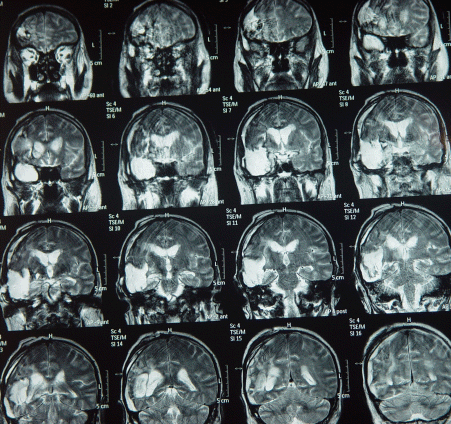

The patient showed steady improvement and the tracheostomy was removed 15-December-2007 and started normal feeding and MRI performed 23-December-2007 showed halt of the aggressive growth of the tumor.

The last picture showing the right MCA eaten by the tumor, despite anatomical preservation during surgery.

The patient underwent radiotherapy, and MRI done 17-Maech-2008 showed no signs of recurrence, still bedridden and can eat well and some times talking and responding to verbal stimuli.

MRI repeated 18-August-2008  showing of the other left hemisphere and involvement of the brain stem in the right side. with deterioration of his condition.

MRI done 04-December-2008 showing enlargement of the right sylvian mass location and down to the vermis. He is completely bedridden and to my knowledge he died 3-4 months later.